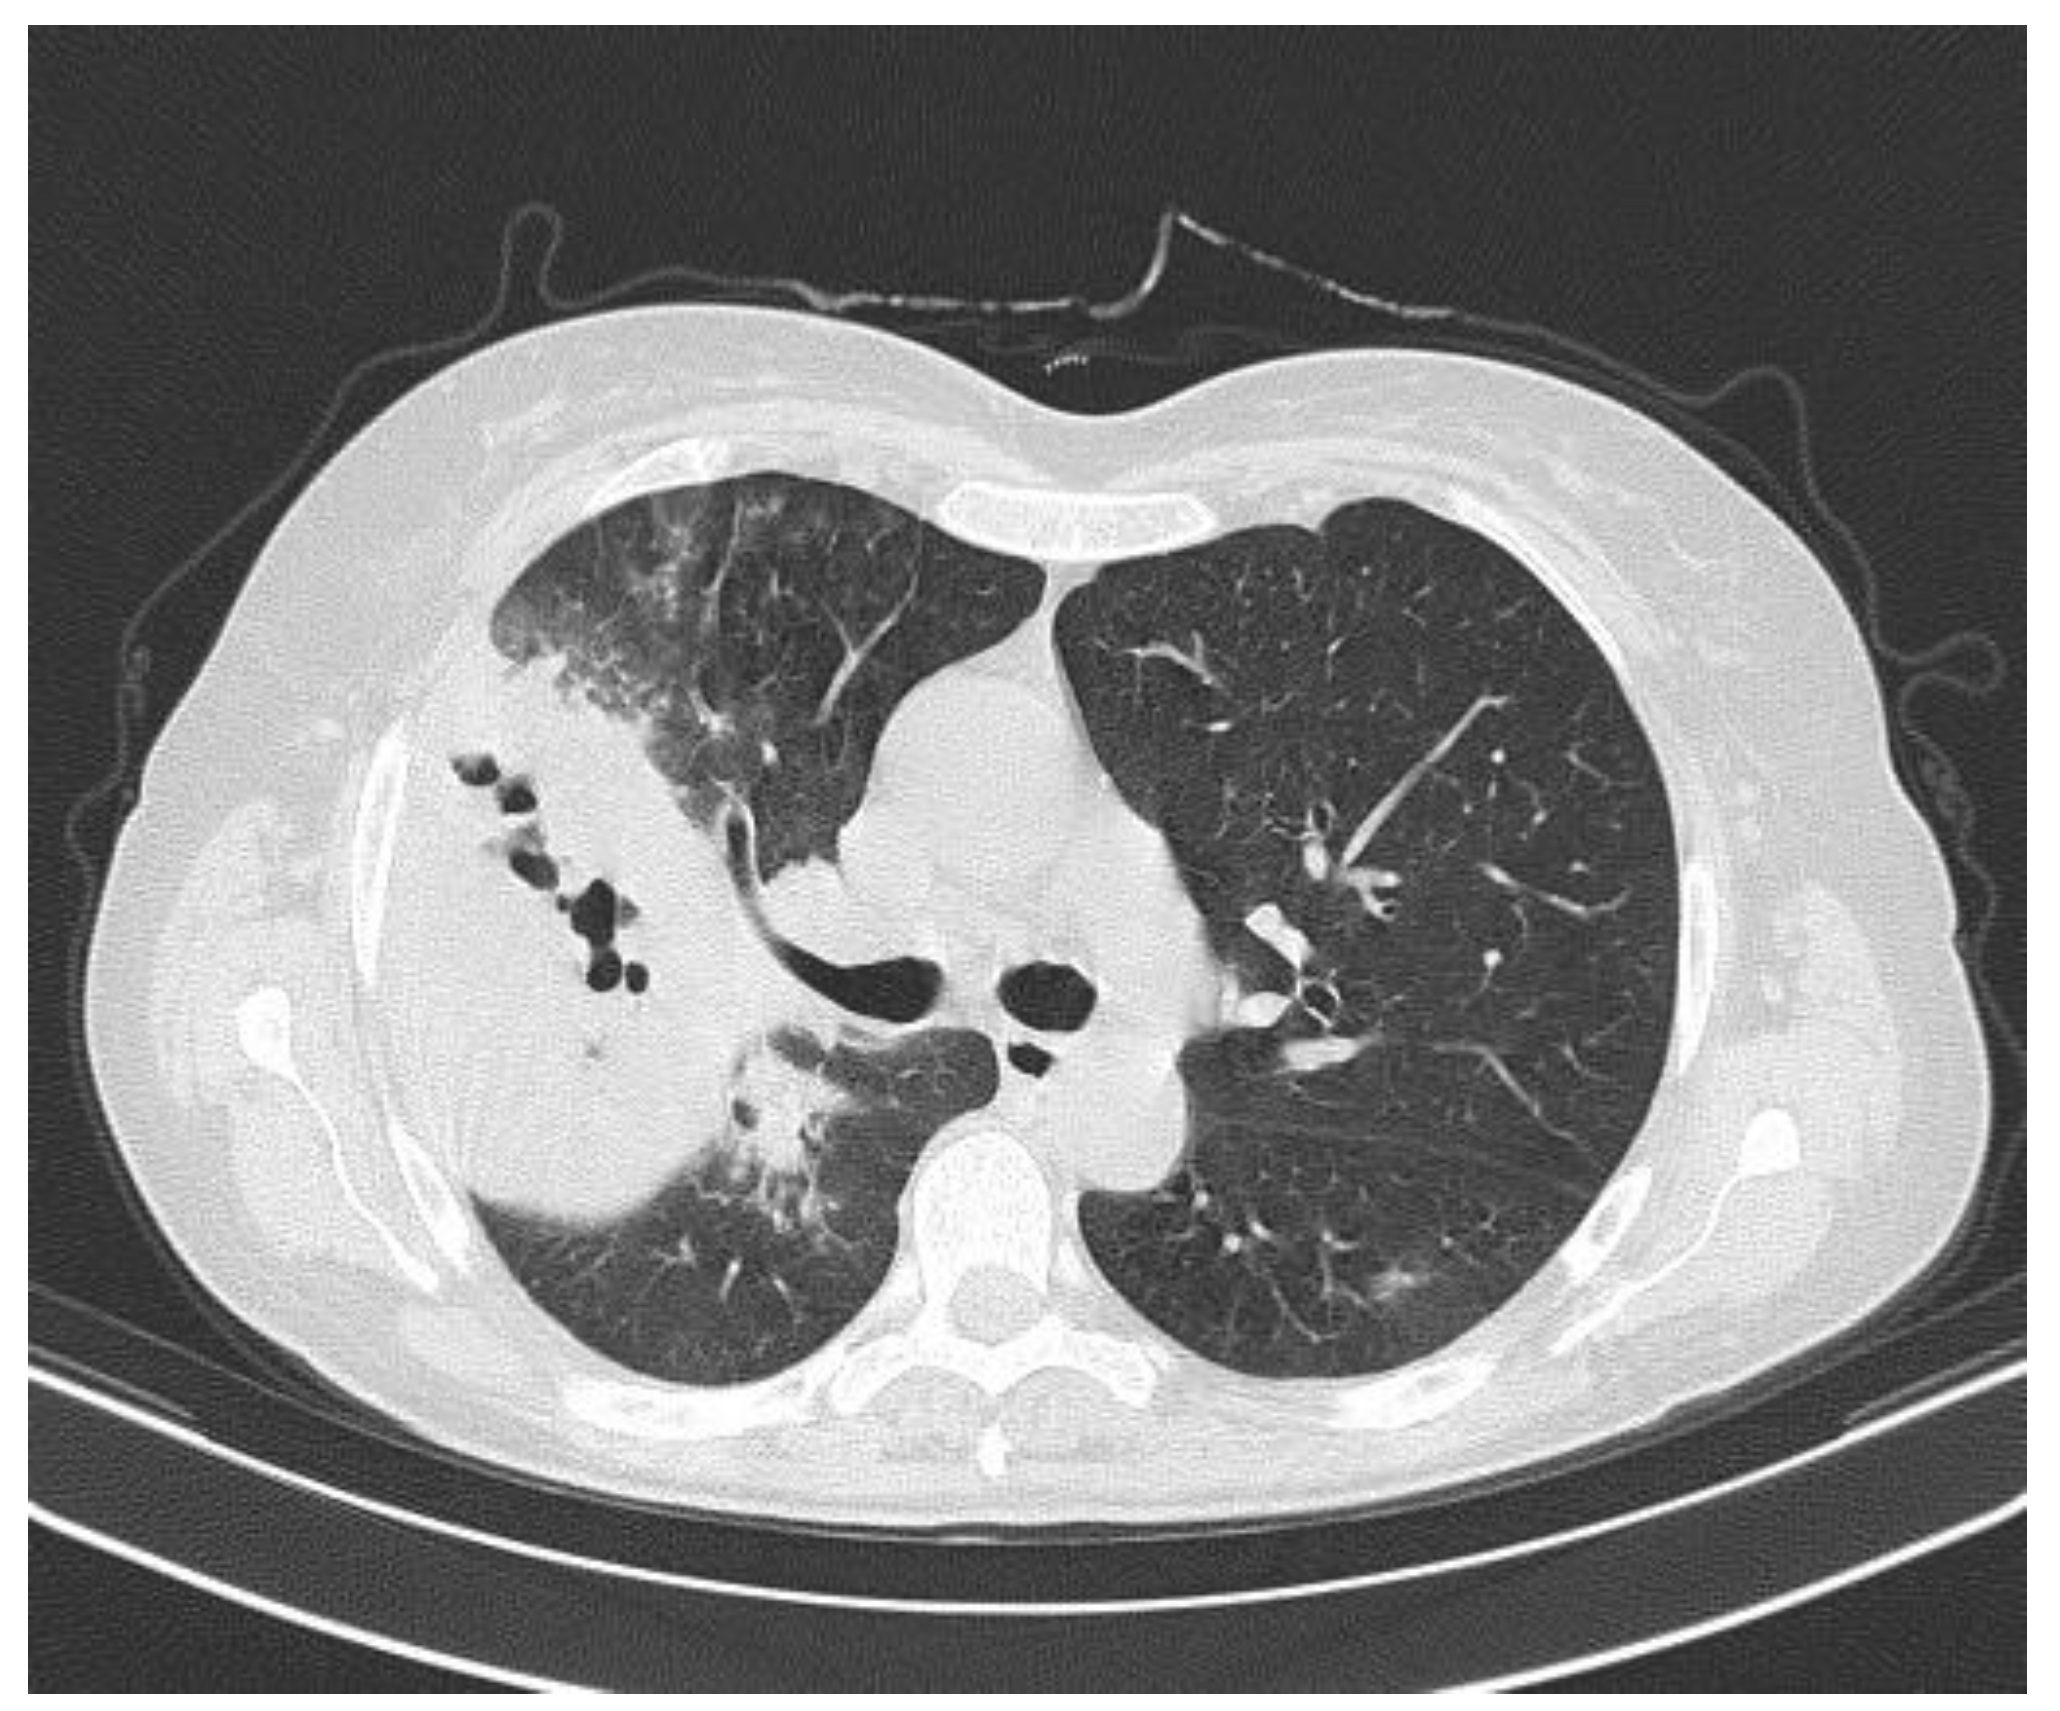

A 57-year-old woman, previously healthy, presented with a 7-day history of cough with brown sputum, sudden onset of chills, subjective fever, malaise and pleuritic pain in the right hemithorax. At admission, the patient was in poor general condition with tachycardia, fever, and tachypnea. Respiratory examination revealed bronchophony in the upper third of the right hemithorax. The initial investigations showed a high C-reactive protein (27.2 mg/dL), leukocytosis (26,700/mm3), neutrophilia (25,200/mm3) and a chest X-ray with a radiopaque image in the right upper lobe (Figure 1). A diagnosis of community-acquired pneumonia was considered, and intravenous antibiotic therapy was started with i.v. clarithromycin 500 mg BID and i.v. ampicillin- sulbactam 3 g QID.

Figure 1.

Chest radiograph with right apical radiopacity.